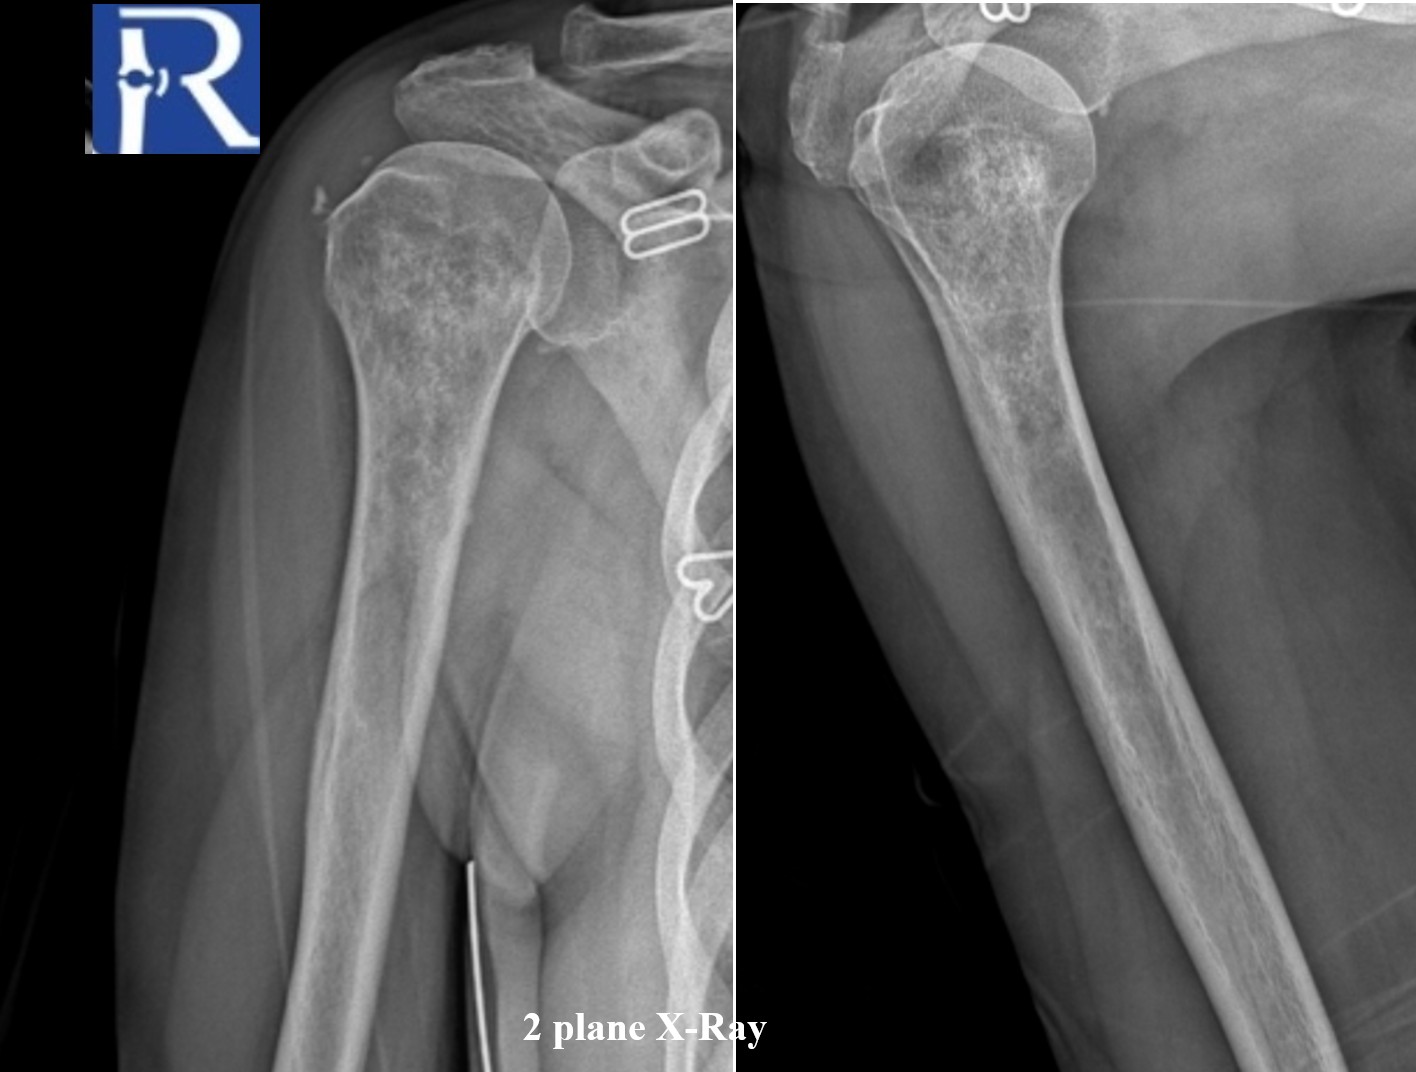

Radiography (Two Views)

- There is a medullary lesion involving the proximal metaphysis and diaphysis of the right humerus.

- The lesion displays a mixed lytic and sclerotic pattern with irregular margins within the medullary cavity.